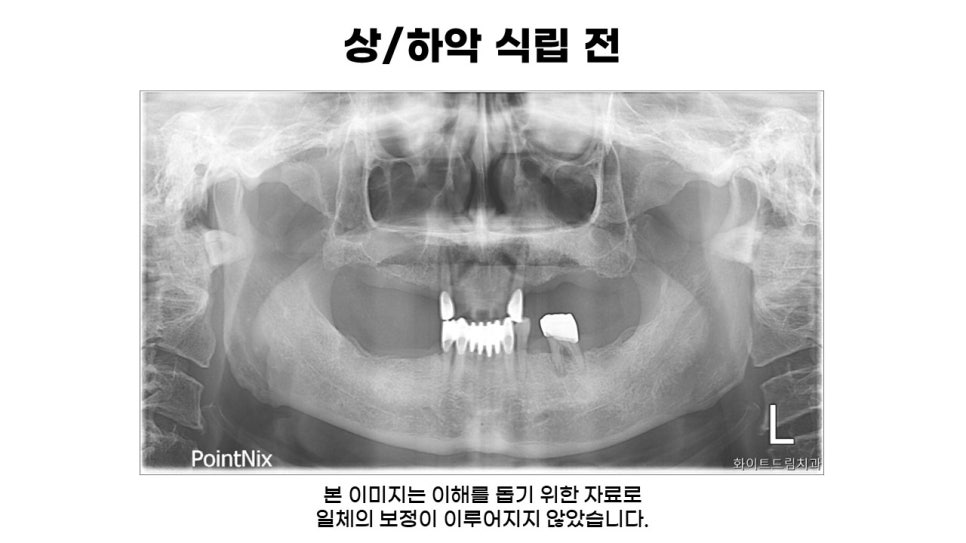

환자분께서는 틀니가 이전에 치료했던 송곳니에 걸어 사용해야 했기 때문에 기존 보철이 많이 흔들리는 상태였으며, 하악 보철 또한 뻗어져 정상교합에서 벗어나 있었습니다.

따라서 환자분 동의 하에 상악 송곳니 발치 후, 상악 풀케이스 및 하악 구치부 일부를 임플란트로 진행하였습니다. 하악 송곳니는 아직 괜찮게 사용하실 수 있을 것 같아 최대한 자연치를 살려 진행했습니다.

식립 전 측면사진을 함께 보시면 늘어난 치주인대로 인해 돌출된 송곳니를 자세하게 파악할 수 있었습니다. 또한, 치아 뿌리와 잇몸뼈를 지탱하지 못하여 치아가 흔들리고 세균을 보호하는 능력이 떨어지게 되어 치주염도 함께 진행되고 있었는데요.

송곳니는 뿌리가 길어 다른 치아에 비해 발치하는 과정에서 난이도가 높은 편에 속하기 때문에 정밀하게 치료하는 것이 중요합니다.